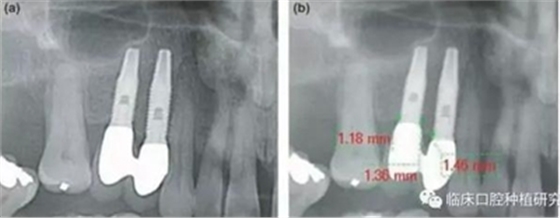

因而,該研究對(duì)隨訪達(dá)5年以上的牙列缺損種植修復(fù)患者,進(jìn)行了觀察性縱向回顧性研究。通過影像學(xué)資料對(duì)比種植體周圍骨吸收和牙周骨吸收,對(duì)其潛在危險(xiǎn)因素,如修復(fù)體設(shè)計(jì)、口腔衛(wèi)生、植體規(guī)格也進(jìn)行了研究。單變量統(tǒng)計(jì)分析結(jié)果發(fā)現(xiàn),性別、種植體系統(tǒng)、拔牙原因、聯(lián)冠修復(fù)、種植體平臺(tái)和修復(fù)體間水平距離與種植體周圍骨吸收有顯著相關(guān)性。多變量統(tǒng)計(jì)分析結(jié)果發(fā)現(xiàn),性別、種植體系統(tǒng)、拔牙原因、聯(lián)冠修復(fù)、種植體平臺(tái)和修復(fù)體間水平距離與種植體周圍骨吸收同樣具有顯著相關(guān)性。其結(jié)果認(rèn)為種植體平臺(tái)和修復(fù)體間水平距離對(duì)種植體周圍骨吸收負(fù)向影響最大,且這一距離適宜在3.3 mm-6 mm。若超出此范圍,則對(duì)種植體周骨吸收不再有影響,但外展隙會(huì)逐漸增大,菌斑堆積增多。